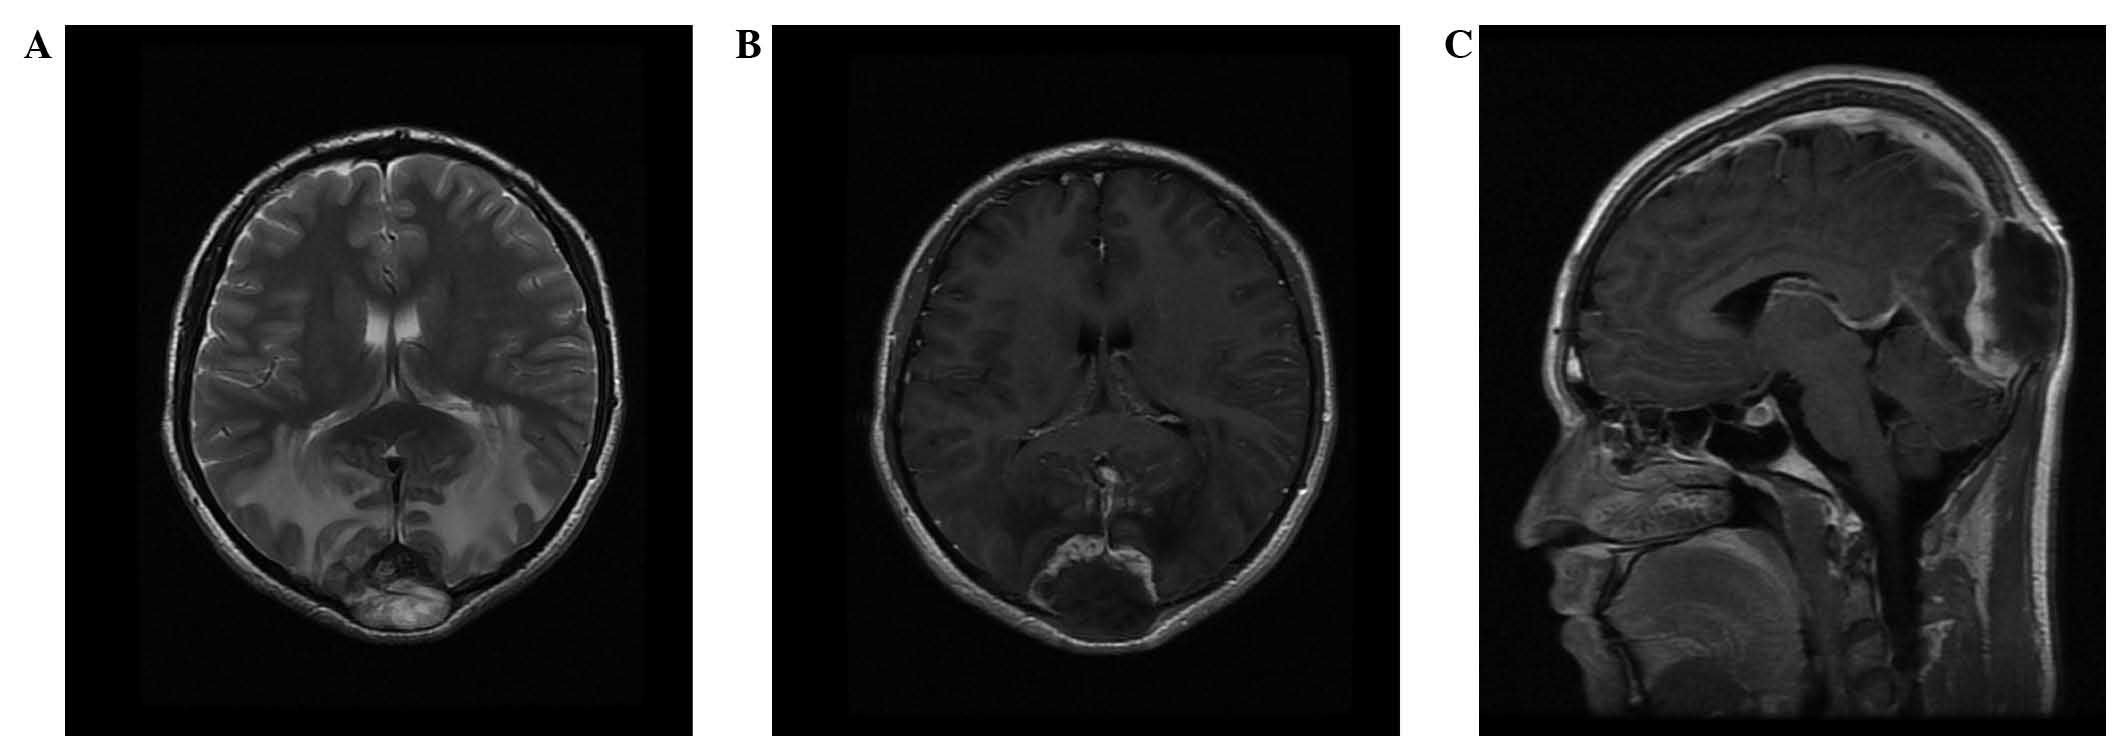

CT imaging (SOMATOM Sensation 16; Siemens Healthcare GmbH, Erlangen, Germany) demonstrated an oval-geographic, osteolytic lesion within the squamous part of the occipital bone, with a well-demarcated intracranial, calvarial and extracalvarial soft tissue mass (Fig. 1). MRI (Signa HDxt 1.5T; GE Healthcare, Fairfield, CT, USA) revealed a focal, 5.0×4.5×3.5-cm mass with bilateral occipital lobe invasion. The mass exhibited hypo- and iso-signal intensity on T1-weighted imaging and mixed-signal intensity on T2-weighted imaging. Gadolinium-enhanced images revealed prominent perilesional enhancement, particularly in the region adjacent to the brain. Irregular hypointense areas within the mass were visible on T2-weighted imaging, without obvious enhancement (Fig. 2). MR venography (Sonata 1.5T; Siemens Healthcare GmbH) was also applied to evaluate the cerebral vein system. MR venography and MRI indicated that the superior sagittal sinus and torcular herophili had been invaded, and associated vasogenic cerebral edema due to mass effect was noted (Figs. 2 and 3).

Figure 2.

Magnetic resonance imaging. (A) Axial T2-weighted images revealed irregular low signal intensity within the mass and cerebral edema in bilateral occipital lobes. (B) Axial and (C) sagittal gadolinium-enhanced images revealed prominent perilesional enhancement, particularly in the region adjacent to the brain.

Radiological findings, although scarce in the literature, were distinctive in the current case. The imaging findings demonstrated a well-defined, heterogeneous, intracranial, calvarial and extracalvarial mass with bone destruction. The osteolytic lesion presented sharp borders, a lack of bony sclerosis and a paucity of periosteal reaction. The adjacent brain and venous sinus were invaded. These appearances may reflect the malignant biological behavior of the tumor. On T2-weighted MRI without enhancement, irregular areas of low signal intensity were visible, a characteristic which may be observed in areas of decreased cellularity and dense fibrous tissue or collagen deposition (10). High signal intensity on T2-weighted images without enhancement is considered to indicate necrosis (11,12). Intense perilesional enhancement of the tumor-adjacent brain region on gadolinium-enhanced MR images may be associated with histopathological changes, which include cellular and vascular proliferation, peritumoral desmoplastic reaction and inflammatory cell infiltration. This enhancement pattern may also be indicative of malignant tumors (13). Therefore, in the current case, imaging findings successfully suggested a tumor of high malignancy containing necrosis and fibrous tissue.